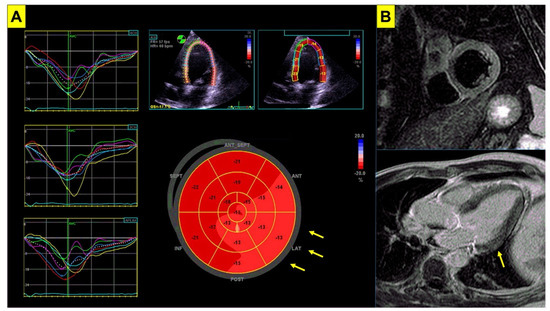

| Echocardiogram - Decreased biventricular function at TEI index through sodium channel blocking test. - Reduction in the RV longitudinal strain. - Morphologic and wall-motion abnormalities of the RV. | [51] [52] [53] |

| Cardiac magnetic resonance - Lower right ventricular ejection fraction. - LV/RV dilation, with a wider involvement of the RV than LV. - Enlarged RVOT area, larger RV end-systolic volumes, lower LV and RV ejection fraction. - Fibrosis and abnormal late fractionated potentials, indicative of slowed conduction in the RVOT region. | [49] [54] [55] [9] |

| Echocardiogram - Focal abnormalities localized in the upper anterior wall but also in the antero-inferior wall. | [70] |